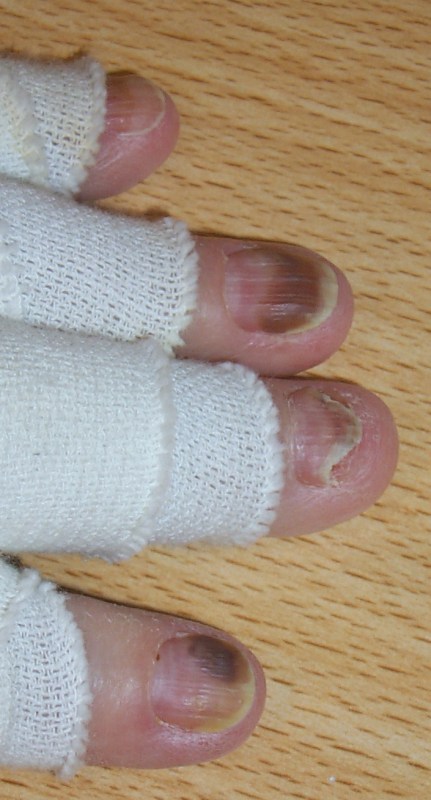

| Nagel | Die Nagelmatrix wird trüb. Der Nagel löst sich

zunehmend ab und kann ausfallen. Zur Stabilisierung wird ein klarer Nagellack empfohlen.![]() |